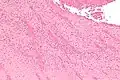

Low magnification micrograph showing laminations in a thrombus in a fatal pulmonary embolism. H&E stain.